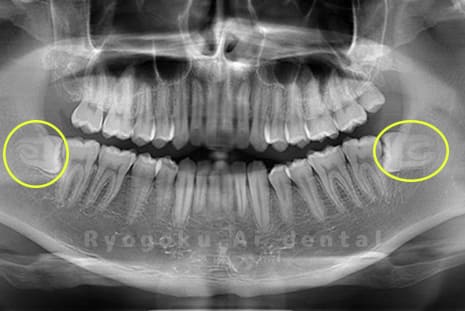

斜めに生えている親知らず

親知らずが斜めに生えて隣の歯にぶつかって圧迫してしまうタイプです。

このタイプが最も多いです。このタイプは虫歯になりやすいだけでなく、隣の歯を圧迫し、咬み合わせや歯並びに影響が出る場合もあるので抜歯をおすすめします。